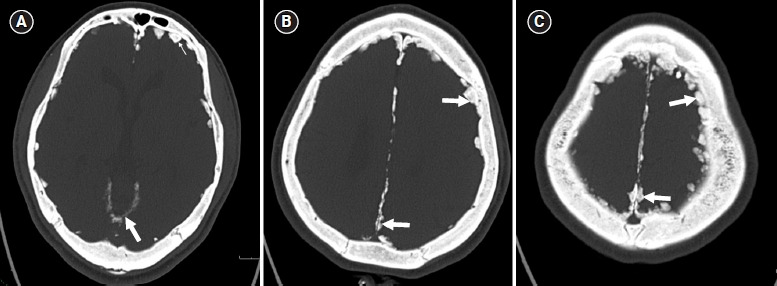

Diffuse incidental dural calcifications.

弥漫性硬膜钙化